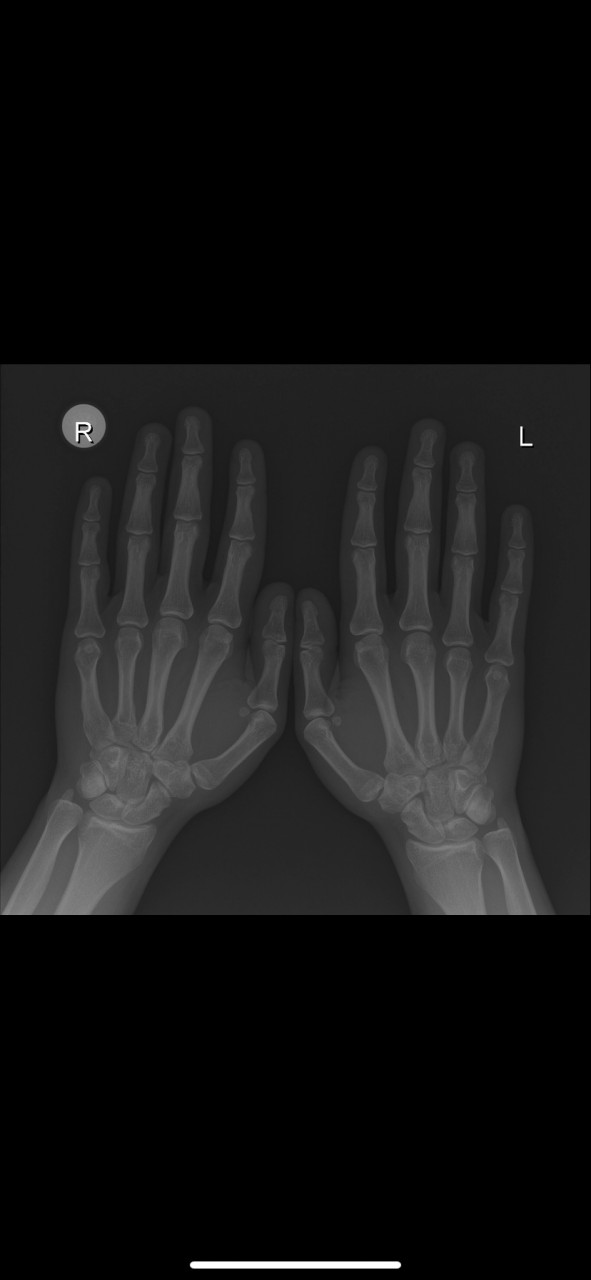

Добрый день. Мне 19. Рост 171. Рост отца 171. Рост матери 165. Смогу ли еще подрасти? Если да, то насколько примерно? Недавно делал рентген, прикрепляю.